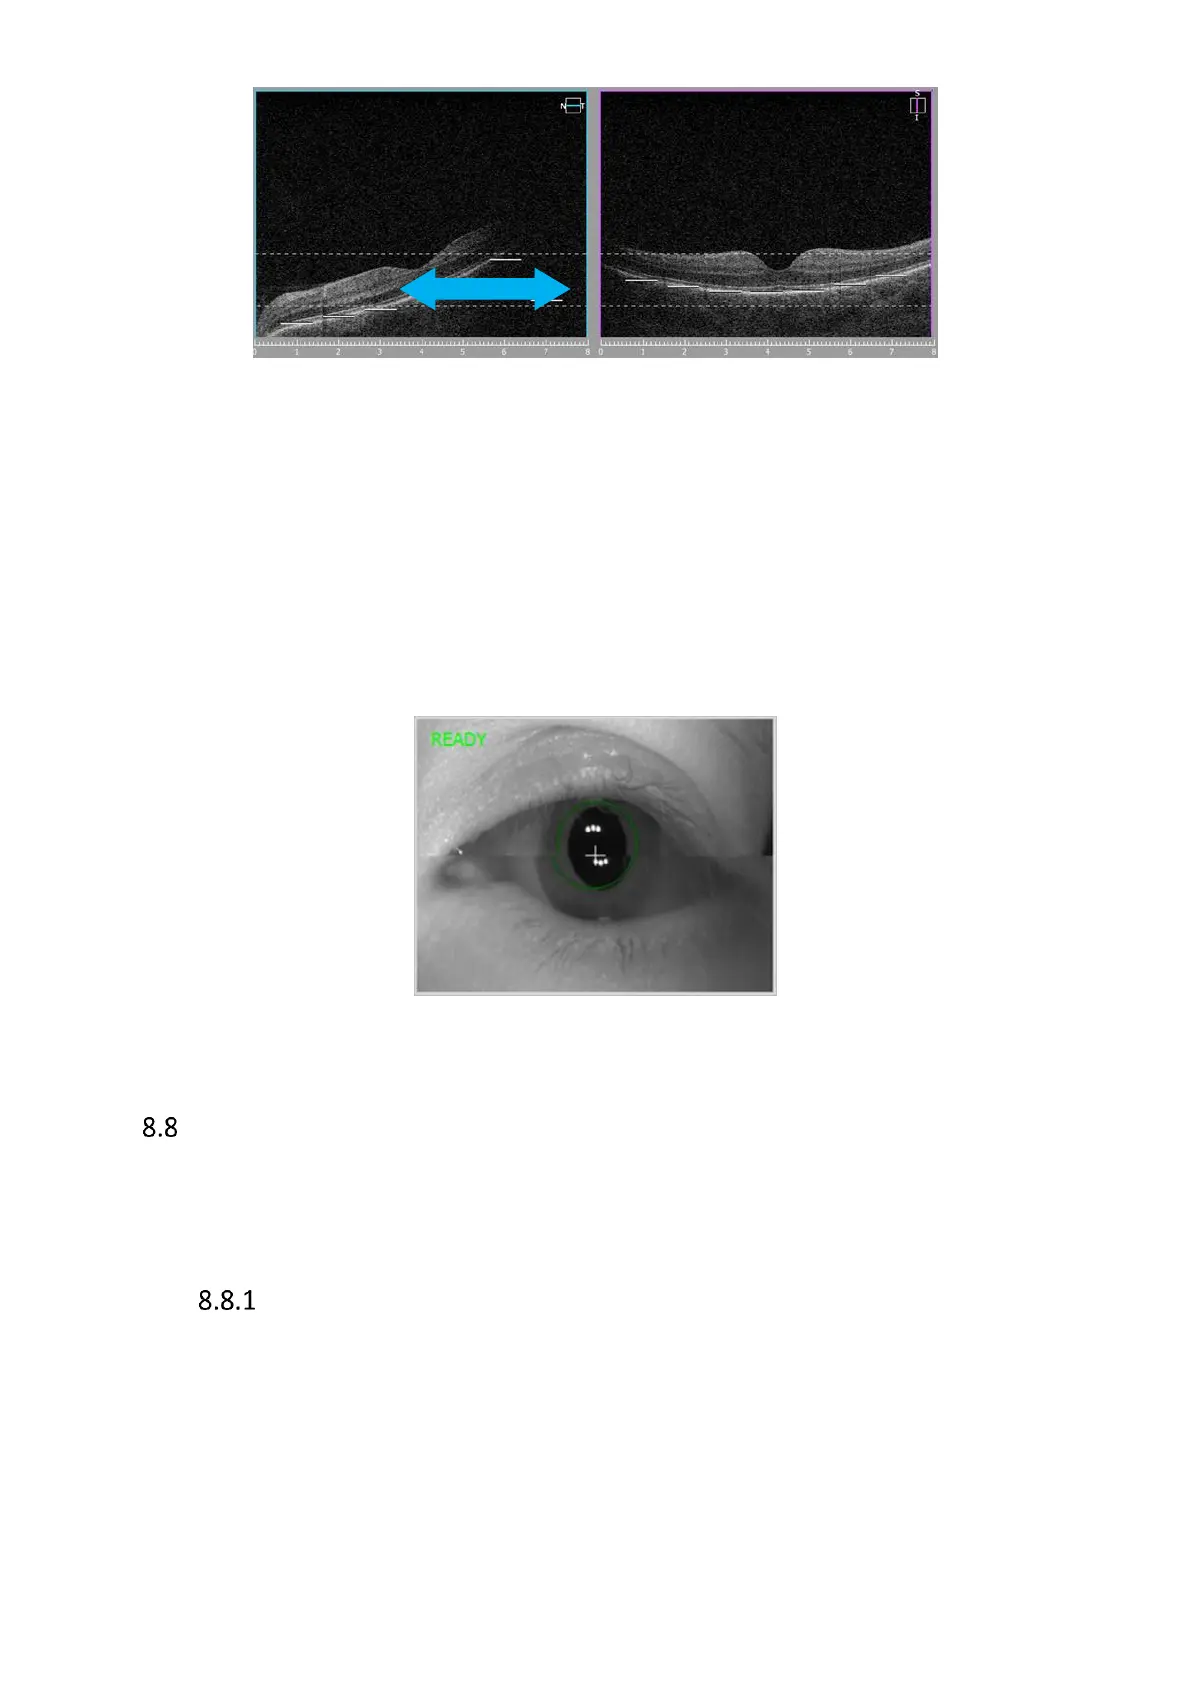

Figure 67. Shadow on tomogram, grab and drag towards right side

Horizontal line in fundus preview window relates to left part of scan preview window. This scan

also should be horizontal. In the case here above the tomogram should be dragged right (head

movement device should be moved right to align scan and remove shadow.

The easiest way to align the tomograms is to drag a tomogram to the proper position.

Figure 68. Proper live eye preview while manual acquire mode